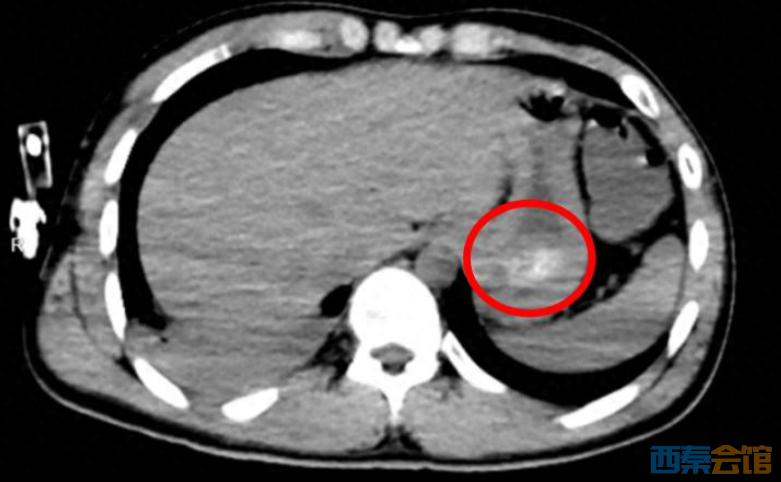

经全腹CT检查证实,林浩胃底存在大量团块状高密度影,也就是常规洗胃无法清除的“药石”,同时胸部CT显示其双肺出现渗出性病变,已引发吸入性肺炎。医生解释:

罪魁祸首就是胃里

持续释放毒性的”药石“

叠加吸入性肺炎

随时可能导致多器官衰竭